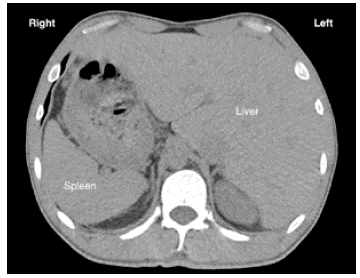

After finding dextrocardia, it was necessary to ascertain visceral situs (normal, inverted, ambiguous). A simple tomography documented pulmonary bronchiectasis, as well as liver on the left side (Figure 4), leading to suspect KS; this was confirmed with findings of chronic sinusitis in paranasal sinus tomography. In addition, HRCT showed tomographic signs of infectious bronchiolitis.

Simple tomography showing that the liver (H) is to the left of the midline and the spleen (B) to the right.

Figure 4: Simple tomography showing that the liver (H) is to the left of the midline and the spleen (B) to the right.

Source: Document obtained during the study.